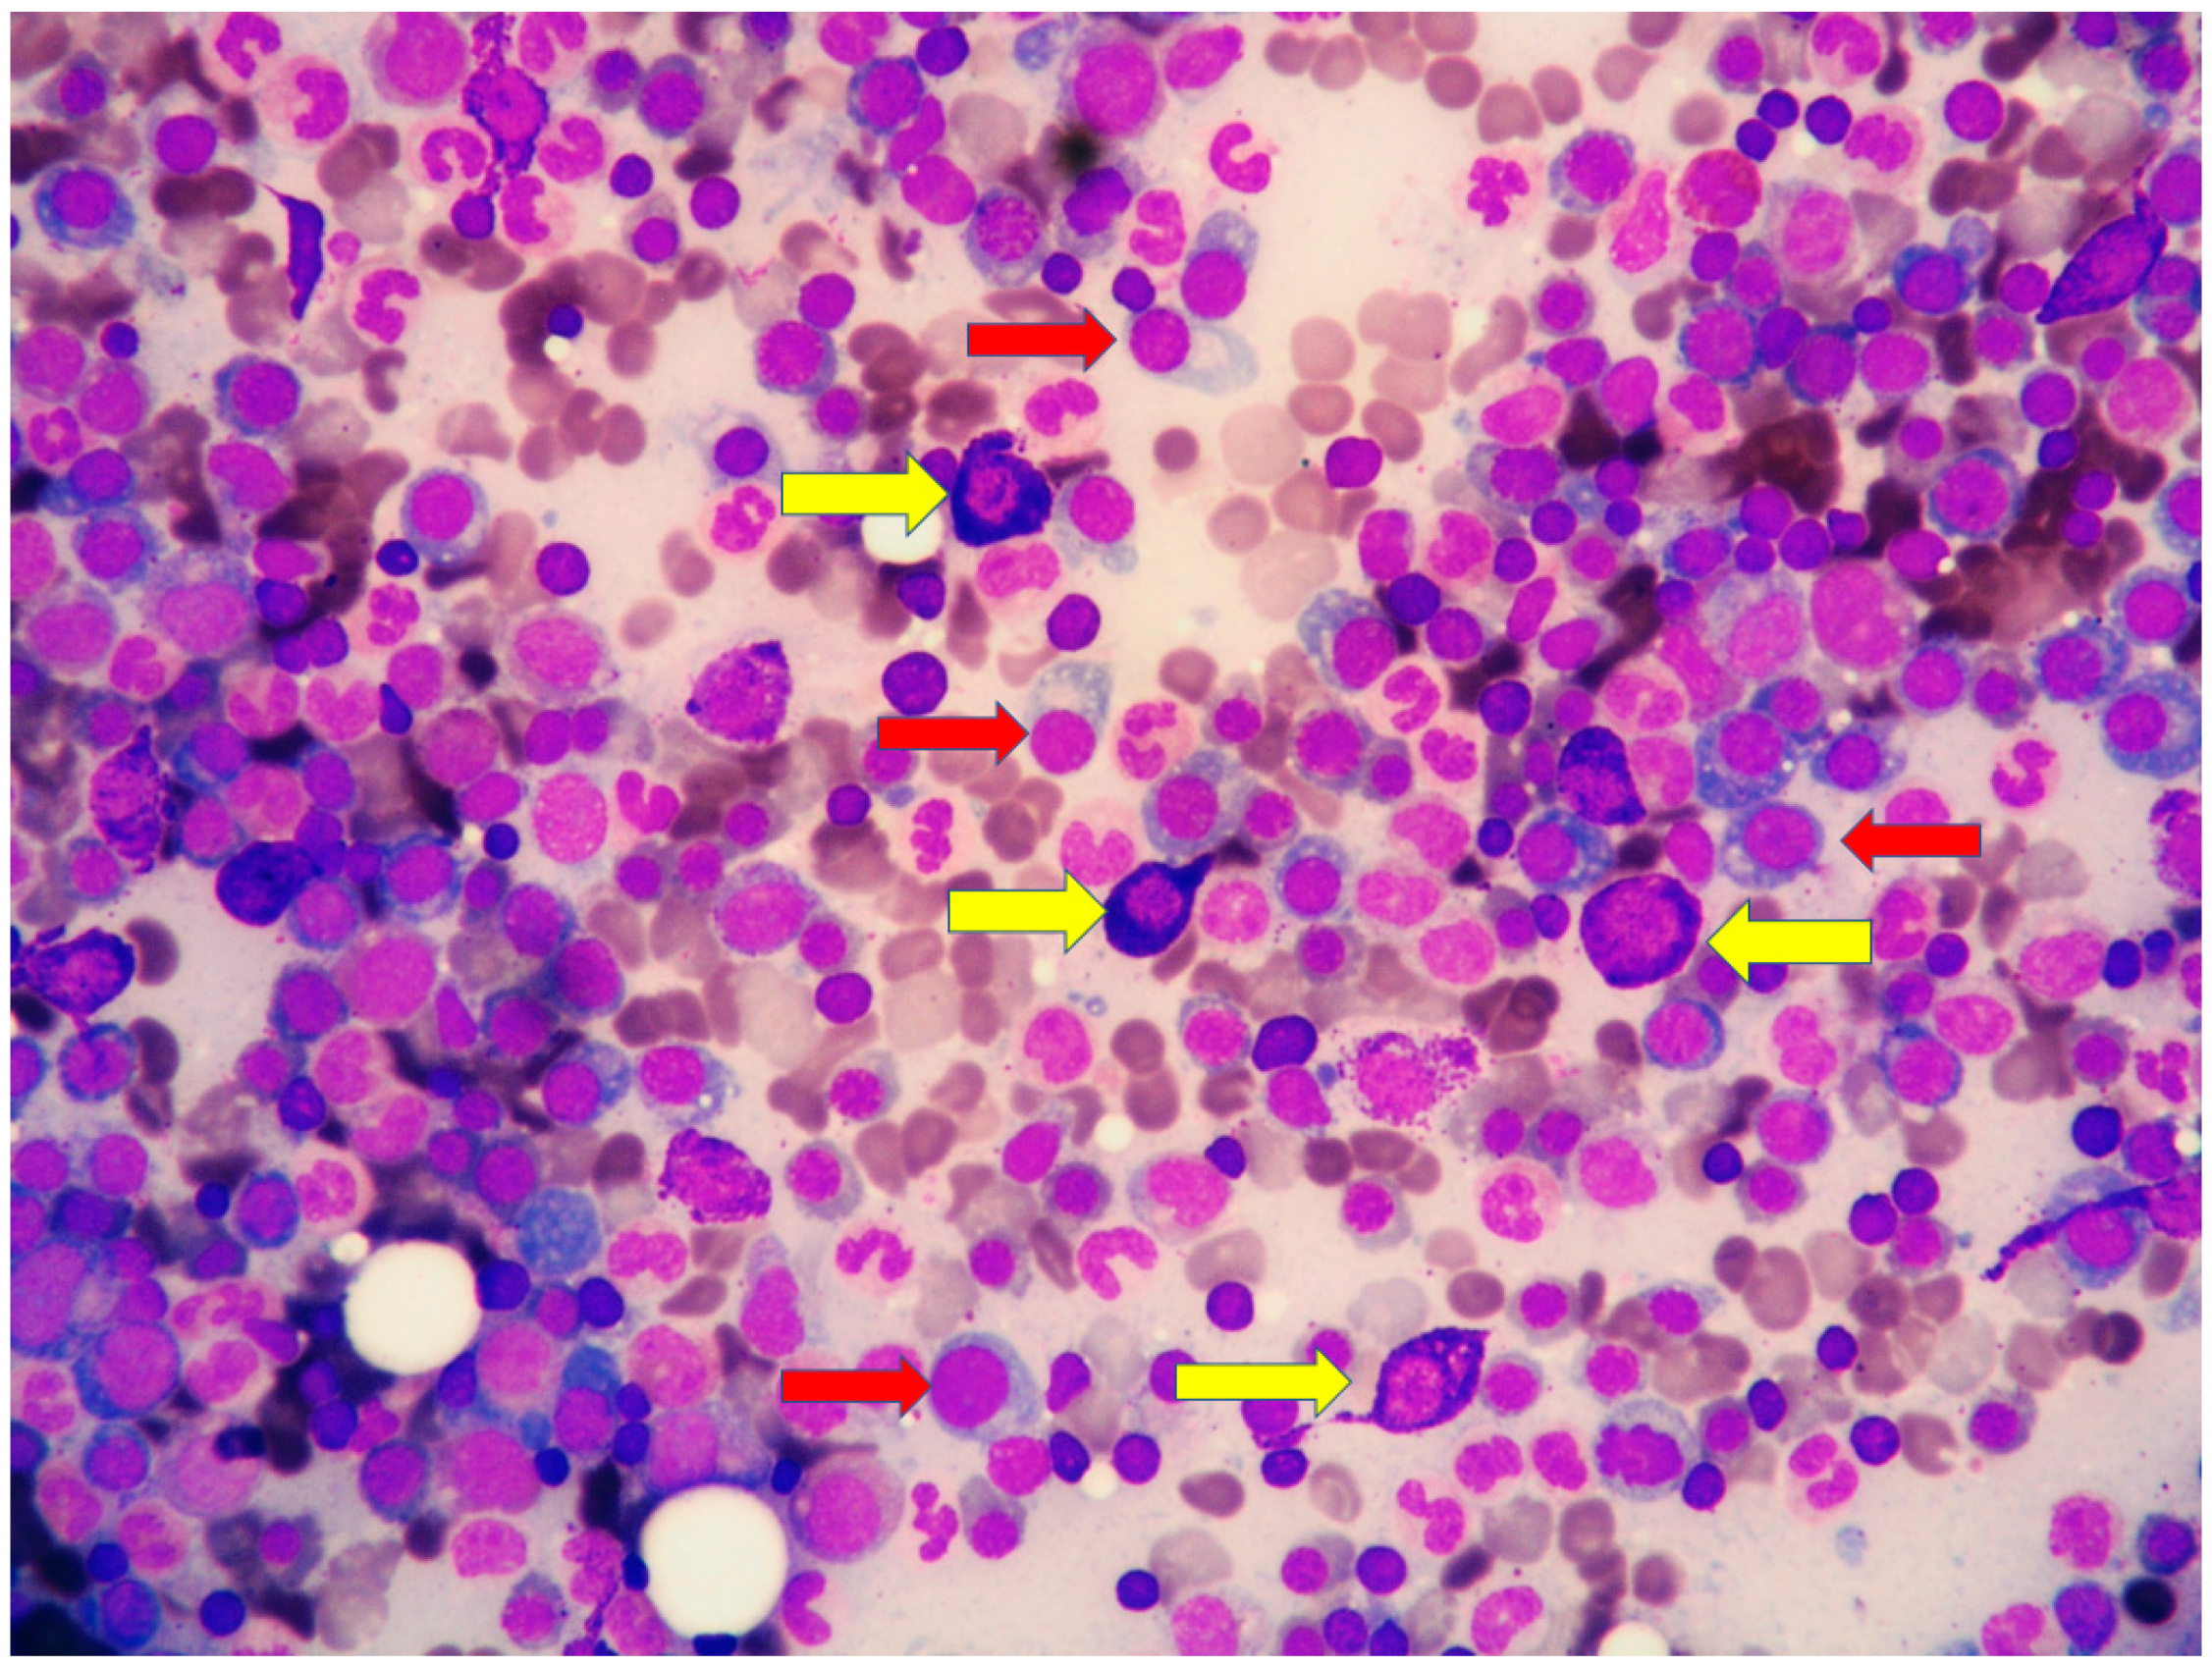

A 79-year-old woman was referred for a long history of peripheral eosinophilia. She underwent right hemicolectomy for colonic polyposis a few years before. Laboratory tests disclosed mild macrocitic anaemia (Hb 10.4 g/dL, MCV 93%) and eosinophilia (leukocytes 3360/mmc, eosinophils 30%). β2 microglobulin (3256 ng/dL; reference range 1010–1730) and serum tryptase (138 ng/L; reference range 0–11.4) were elevated. Serum immunofixation revealed IgA/kappa monoclonal protein (21 g/L). Bence-Jones protein was positive. Bone marrow (BM) biopsy revealed two neoplastic components. Low- and high-power views of haematoxylin and eosin sections showed cohesive paratrabecular aggregates of bland-looking, spindle-shaped cells (

Figure 5). KITD816V mutation was detected by DHPLC and confirmed by Sanger sequencing; TET2 mutation was identified using DNA sequence analysis on marrow aspirate. Monoallelic deletion of TP53/17p13 and trisomy of ATM/11q23 was detected by FISH analysis on BM enriched with plasma cells using CD138+ magnetic Micro-Beads, respectively, in 39% and 94% of nuclei. RUNX1, ASXL1, SRSF2 and U2AF1 were unmutated. Osteoporosis was identified by full skeletal X-rays and MRI. The case was referred to as SM with concomitant smoldering MM.

The diagnosis of SM was proposed owing to the fulfilment of the major diagnostic criteria (multifocal, dense, compact aggregates in bone marrow and/or extra-cutaneous organs) and three of the minor criteria (KIT D816V mutation, CD25 expression, serum tryptase level exceeding 20 ng/mL) combined with the presence of a C finding (organ involvement with loss of function: intestinal mastocytosis with clinical malabsorption identified in the previous colectomy specimen) [

1]. Due to the bone marrow findings, along with the absence of myeloma-defining events (frank anaemia, hypercalcemia, lytic bone lesions, renal insufficiency secondary to myeloma, recurrent bacterial infections, blood hyperviscosity, paraneoplastic neuropathy, signs of associated amyloidosis, spinal osseous lesions at MRI), our patient fitted into the diagnosis of smoldering MM.

The coexistence of SM with MM placed our patient in the SM with associated clonal haematological non-mast-cell lineage disease (SM-AHN) subtype. Midostaurin therapy (100 mg twice per day) was started.